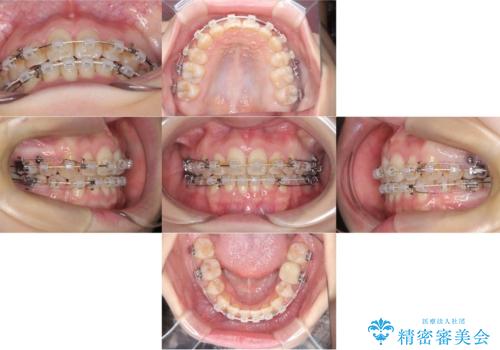

- 「歯のデコボコ、八重歯、口ボコが気になる」を主訴に来院された患者様です。

上下左右4番(4本)の歯を抜歯しワイヤー矯正で治療を行いました。

計4本の抜歯を行い、歯のデコボコと口元がすっきりし、大変ご満足していただけました。